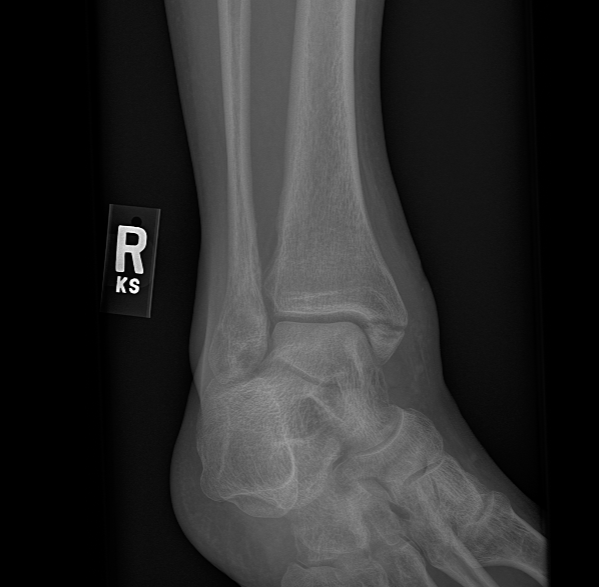

"In September of 2021 I suffered a trimalleolar fracture of my right ankle in a freak accident. That was on a Saturday, and early Monday morning I was seen by Dr. Harrod, who said that surgical intervention would be required. He operated on my ankle that Thursday, inserting two metal plates and several pins. For two months I could not put any weight on that foot, and for several weeks after that I was in a walking boot. I began regular physical therapy in January of 2022, and now, in late May, I walk several miles a day and keep up an exercise and stretching routine. I still experience some soreness and swelling in the ankle, but I look forward to spending this summer teaching in Vermont and hiking, swimming, and riding my bike."